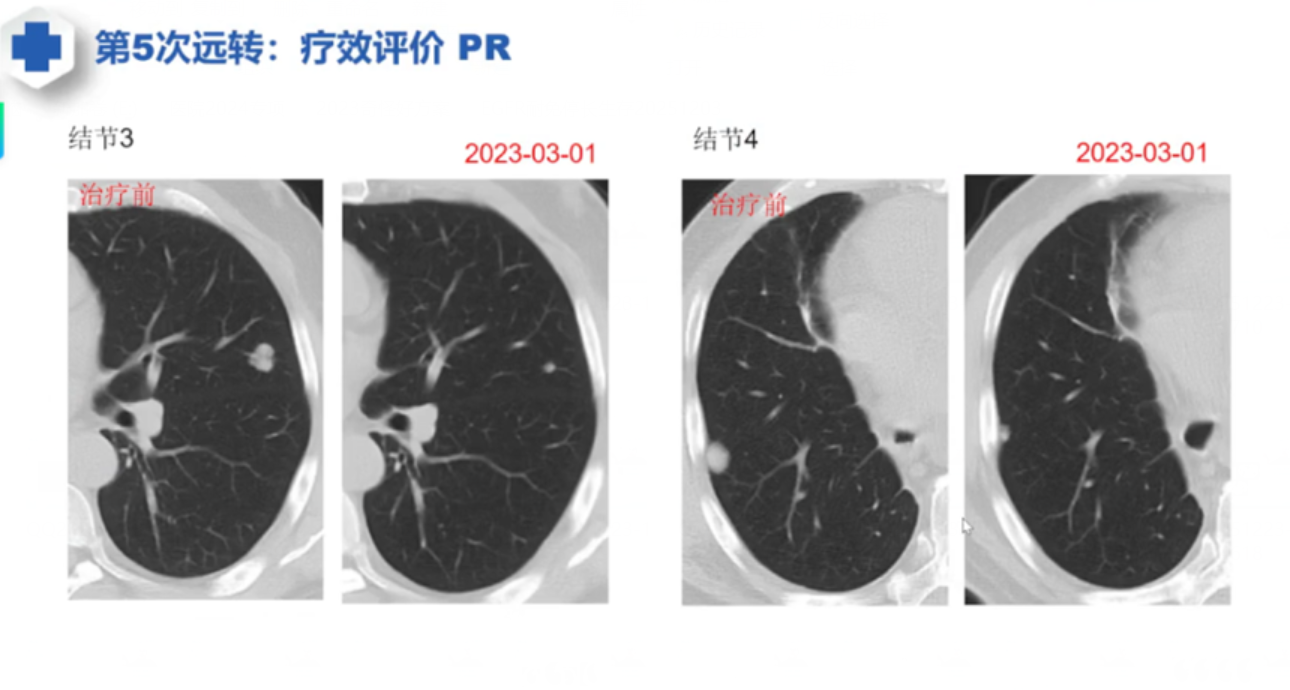

参考案例,一切皆有可能

这个问题笼统的说,很复杂,比较难回答。。。。随便给你个参考案例,一切皆有可能。